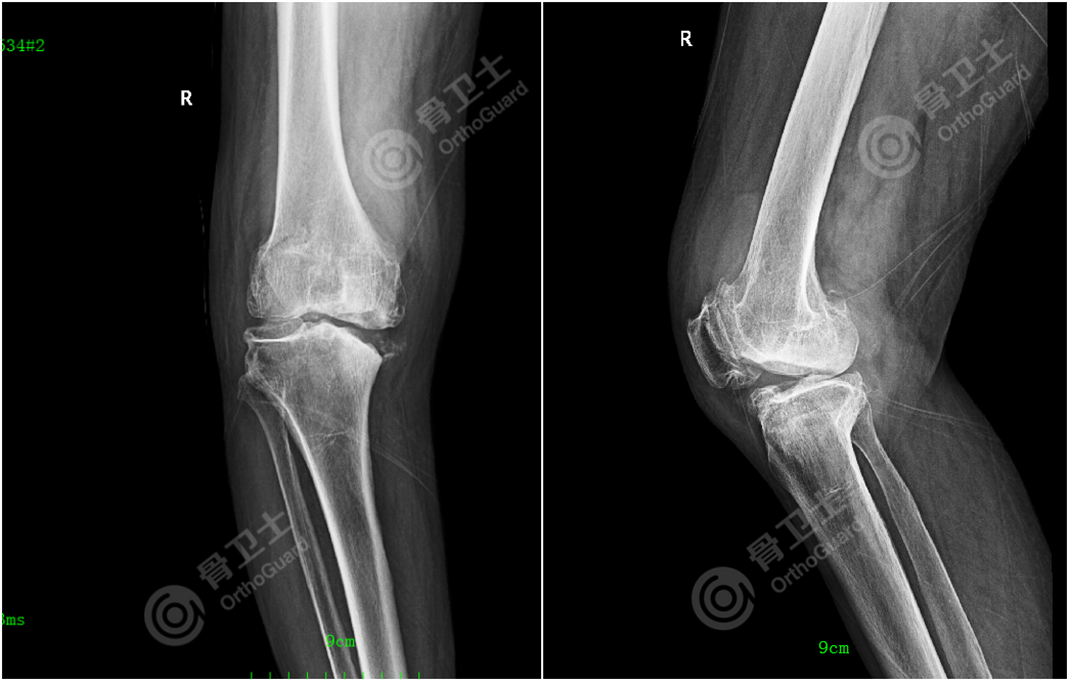

▲患者术前CT+骨三维

考虑到患者双膝骨关节炎退变严重,右膝为重,长时间的膝内翻畸形,导致右膝关节双侧副韧带松弛,关节不稳;双膝关节活动度差,关节活动受限严重,股四头肌及膝关节后侧肌力萎缩;内侧胫骨平台软骨磨损严重,并内侧骨质缺损,各种因素叠加,增加了手术难度。

查振刚教授带领团队为患者进行会诊,仔细询问患者病史、查体,研究患者影像资料,经过分析讨论,决定为患者行右膝关节全膝关节置换术,在内侧平台给予螺钉打桩支持。